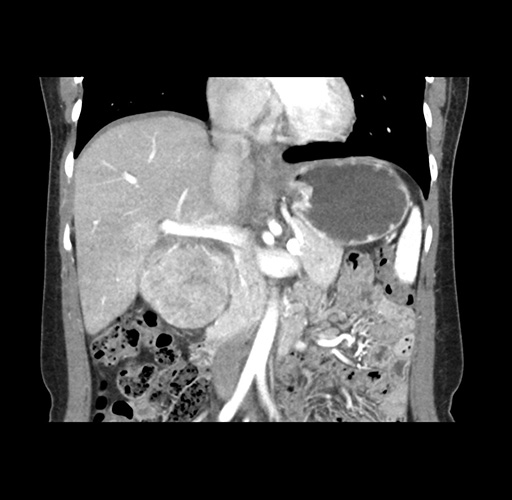

Imaging Analysis

Look through the patient's CT scan to identify any areas of concern for the necessary procedure.

Based on your CT findings, which issue(s) would give reason for "planned slowing down moment(s)" in this case?

Considering a standard left lateral sectionectomy procedure, what step(s) of the operation would you do differently in this case ?